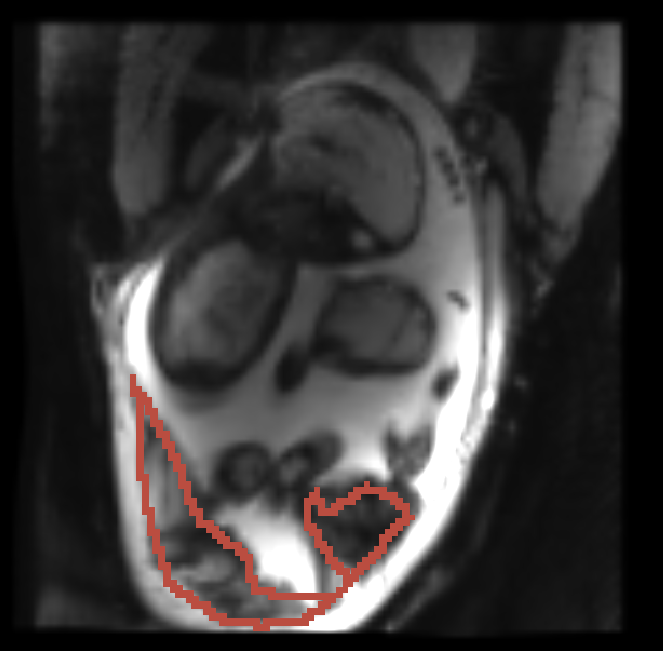

, manual segmentation on , manual segmentation on , propagated segmentation

, manual segmentation on , manual segmentation on , manual segmentation on

Fig. 3 provides example results from the study for fetal brains and placentae. We observe that the reference frame is warped accurately by the temporal registration algorithm in the regions of fetal brains and placentae to represent the first frame in the series that is substantially different from the template. The delineations achieved by transferring manual segmentation labels from the reference frame to the coordinate system of the selected frame are in good alignment with the manual segmentation outlines for that selected frame.